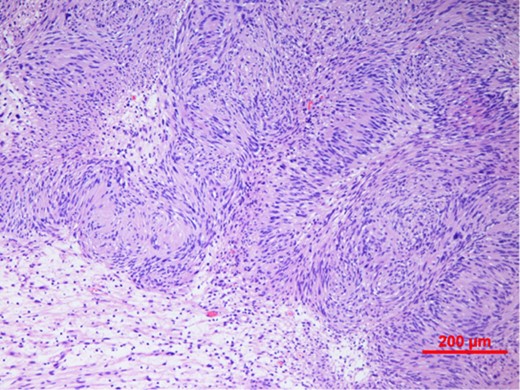

Our patient underwent an excisional biopsy without a preoperative needle biopsy. A 1.2 × 1.2 × 0.8 cm smooth well-encapsulated nodule was removed in entirety from the breast parenchyma. On bisection, the cut section displayed a pale pink smooth homogeneous appearance. Microscopic evaluation showed an encapsulated spindle cell tumour with prominent nuclear palisading and features typical of a schwannoma (Fig. 3). There was also strong and diffuse positive staining of S-100, favouring the diagnosis of schwannoma (Fig. 4). There was no evidence of malignancy in the specimen.

Spindle cell tumour with palisaded arrangement of nuclei, typical of schwannoma. Cellular (Antoni A) areas alternate with looser myxoid (Antoni B) areas.